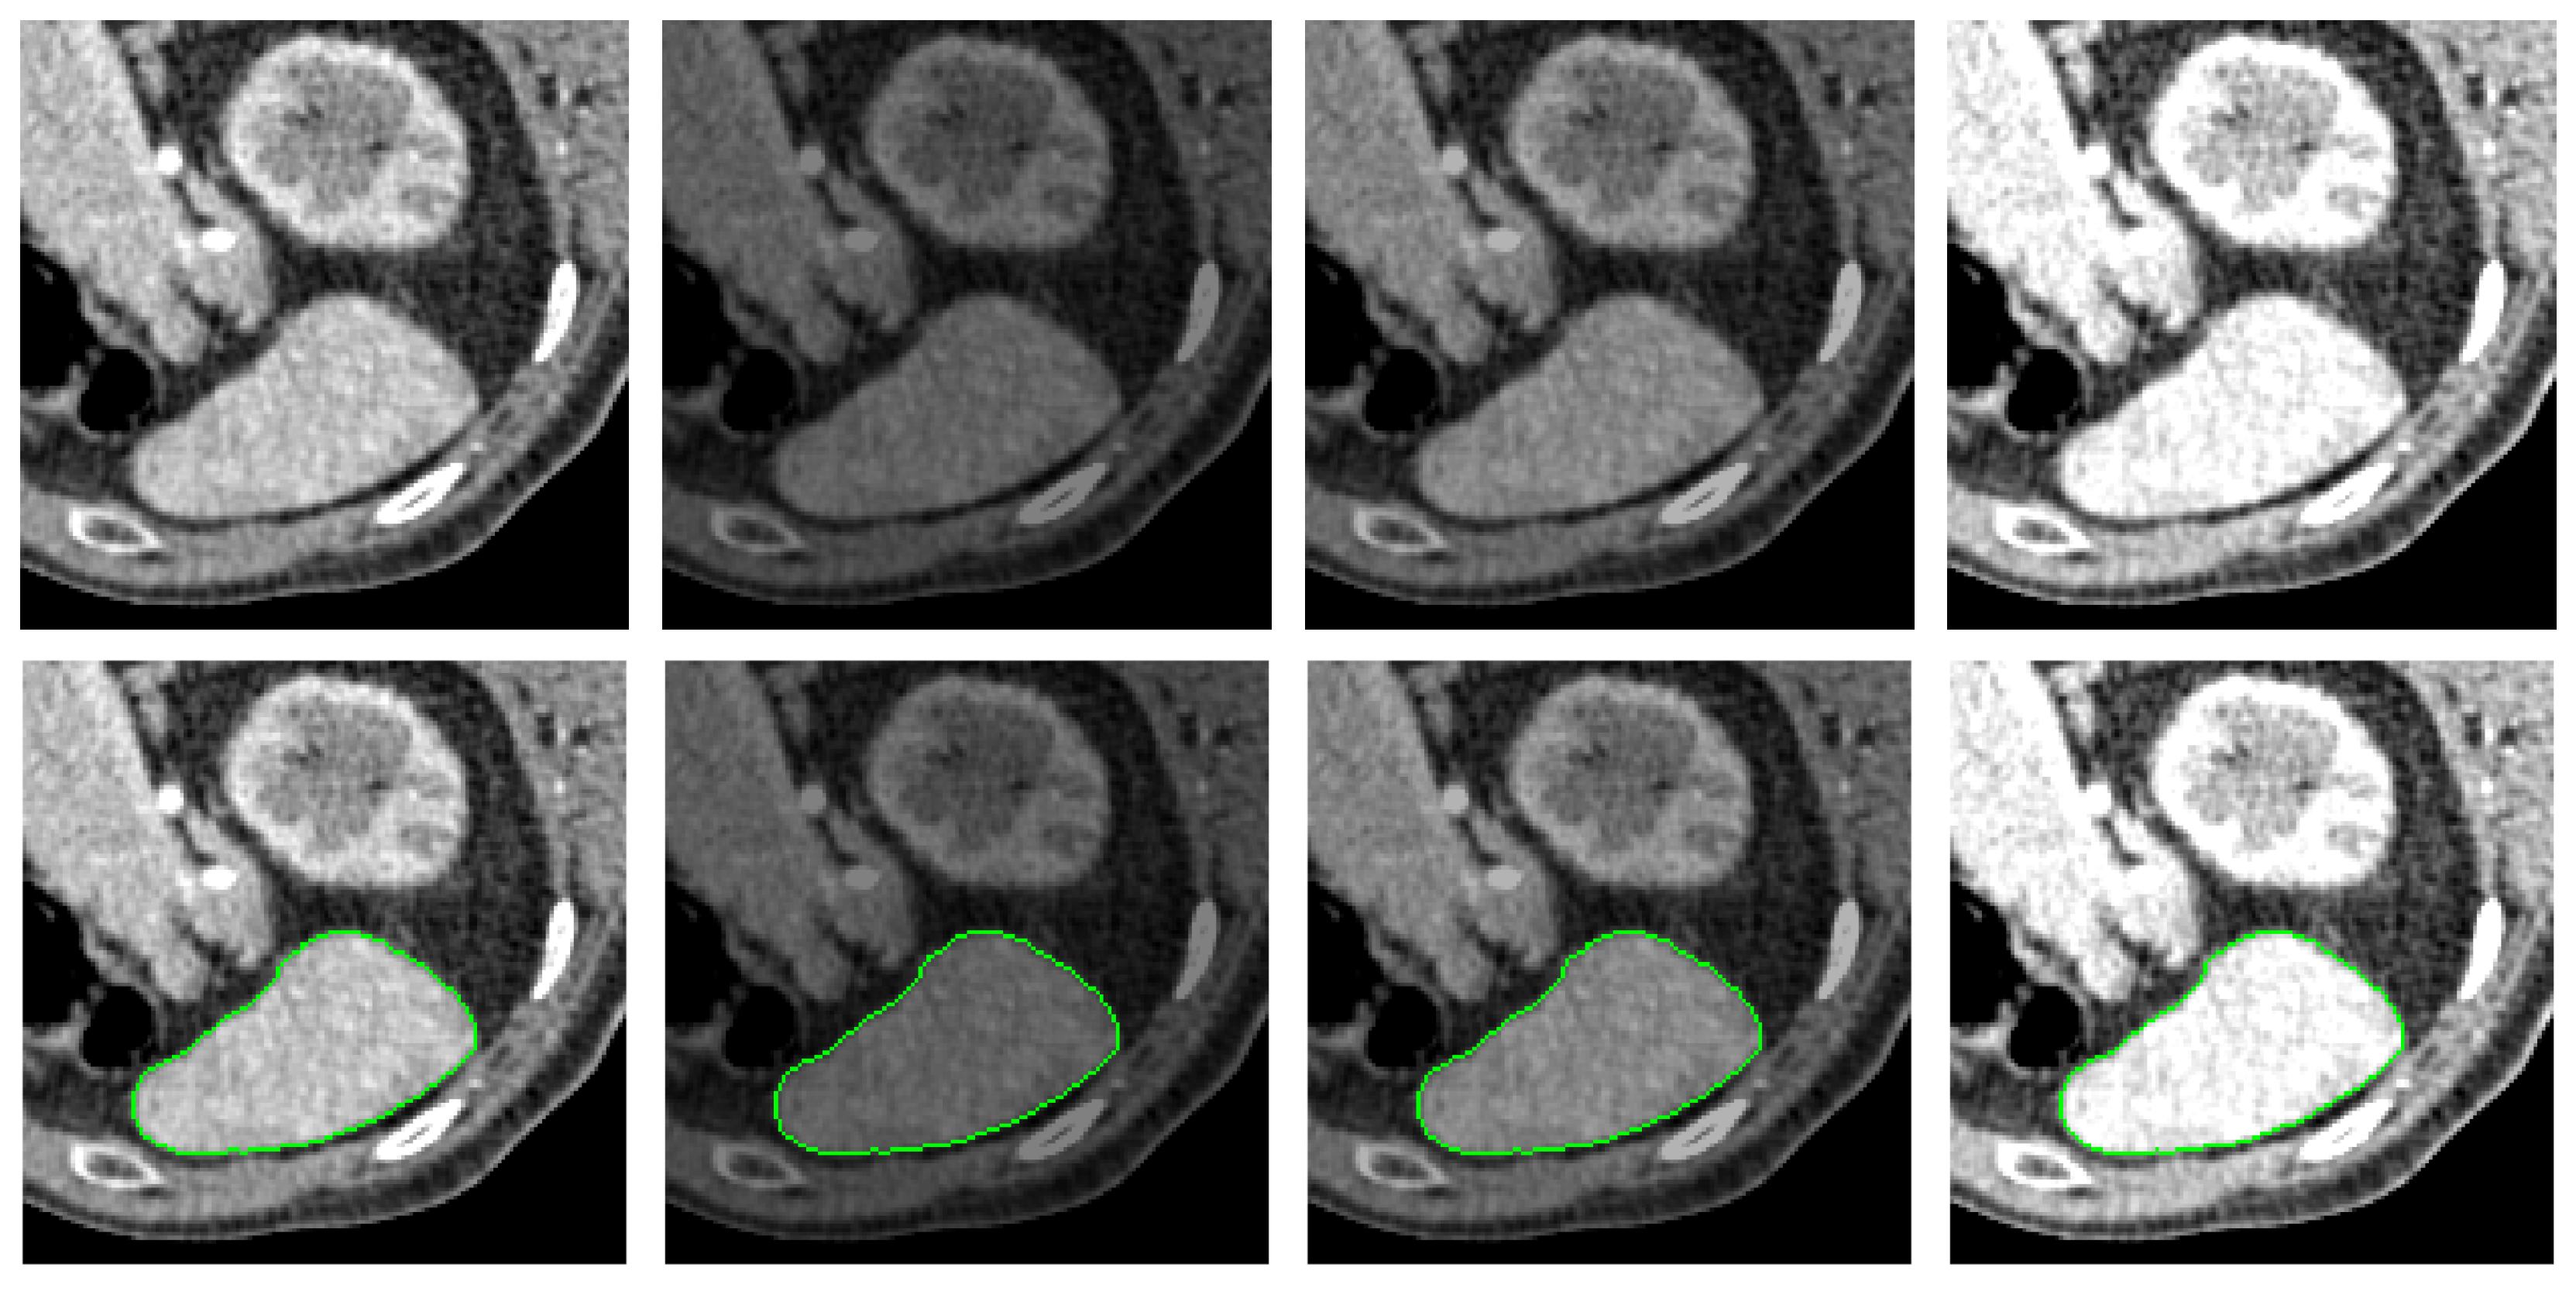

4.2. Qualitative Comparison Analysis

- Medical Images: For medical images, we select X-ray computed tomography (CT) scans from [41]. This dataset is commonly used in medical image segmentation evaluations, with image resolution ranging from to pixels, depending on the specific context of each test.

- The PolarMask model does not incorporate contour regularization. In scenarios where image quality is low or distorted by noise, such as in medical CT images, the absence of regularization can lead to unexpected and irregular segmentation results, highlighting significant room for improvement.

- The efficacy of the proposed PolarVoting model is evaluated on both real-world natural and medical images. Experimental results demonstrate that the PolarVoting model indeed outperforms both PolarMask and the traditional single-source CGV model, underscoring its effectiveness across varied contexts.